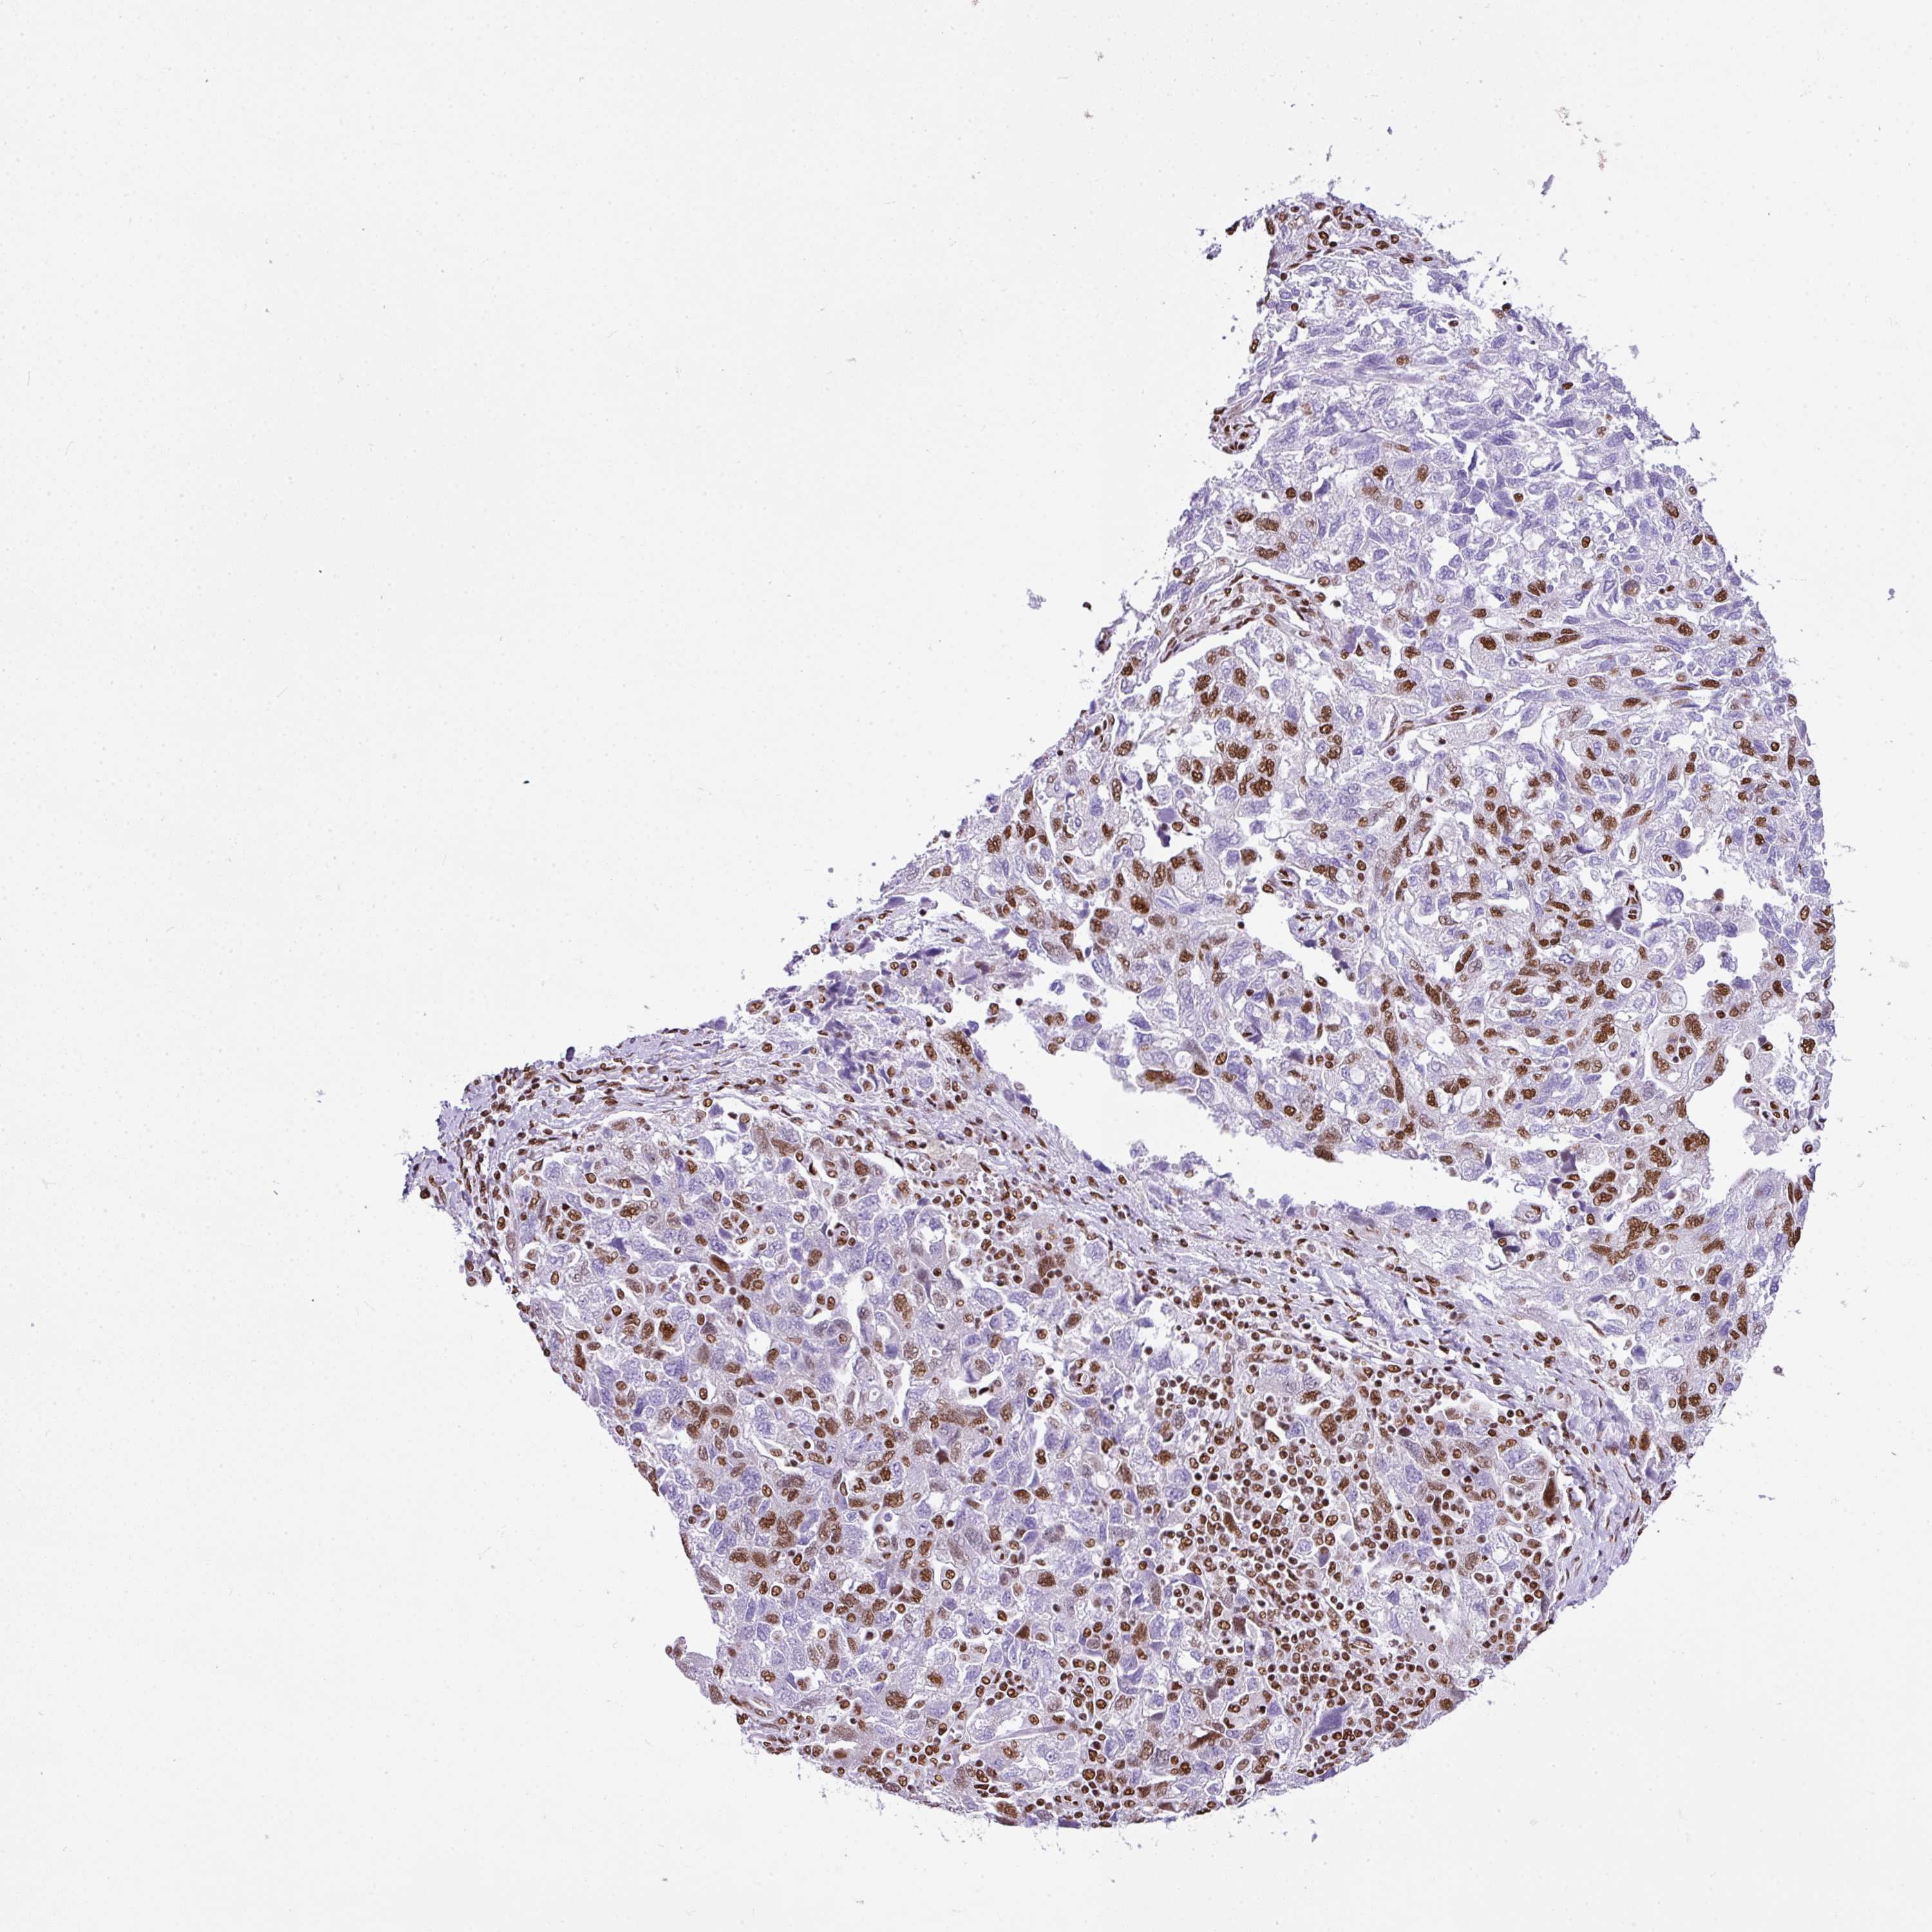

OVARIAN CANCER - Protein expressioni

A mouse-over function shows sample information and annotation data. Click on an image to view it in a full screen mode. Samples can be filtered based on level of antibody staining by selecting one or several of the following categories: high, medium, low and not detected. The assay and annotation is described here.

Note that samples used for immunohistochemistry by the Human Protein Atlas do not correspond to samples in the TCGA dataset.

Antibody stainingi

Antibody staining in the annotated cell types in the current human tissue is reported as not detected, low, medium, or high, based on conventional immunohistochemistry profiling in selected tissues. This score is based on the combination of the staining intensity and fraction of stained cells.

Each image is clickable and will lead to virtual microscopy that enables deeper exploration of all samples and also displays staining intensity scores, fraction scores and subcellular localization as well as patient and tissue information for each sample.

Antibody HPA053883

Staining

High

Medium

Low

Not detected

Intensity

Strong

Moderate

Weak

Negative

Quantity

>75%

75%-25%

<25%

None

Location

Nuclear

Cytoplasmic/membranous

Cytoplasmic/membranous,nuclear

Cystadenocarcinoma, serous, NOS

Carcinoma, NOS

Cystadenocarcinoma, mucinous, NOS

Carcinoma, endometroid